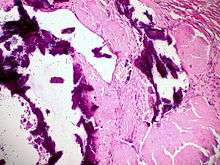

Dystrophic calcification (DC) is the calcification occurring in degenerated or necrotic tissue, as in hyalinized scars, degenerated foci in leiomyomas, and caseous nodules. This occurs as a reaction to tissue damage,[1] including as a consequence of medical device implantation. Dystrophic calcification can occur even if the amount of calcium in the blood is not elevated. (A systemic mineral imbalance would elevate calcium levels in the blood and all tissues and cause metastatic calcification.) Basophilic calcium salt deposits aggregate, first in the mitochondria, and progressively throughout the cell. These calcifications are an indication of previous microscopic cell injury. It occurs in areas of cell necrosis in which activated phosphatases bind calcium ions to phospholipids in the membrane.

Calcification in dead tissue